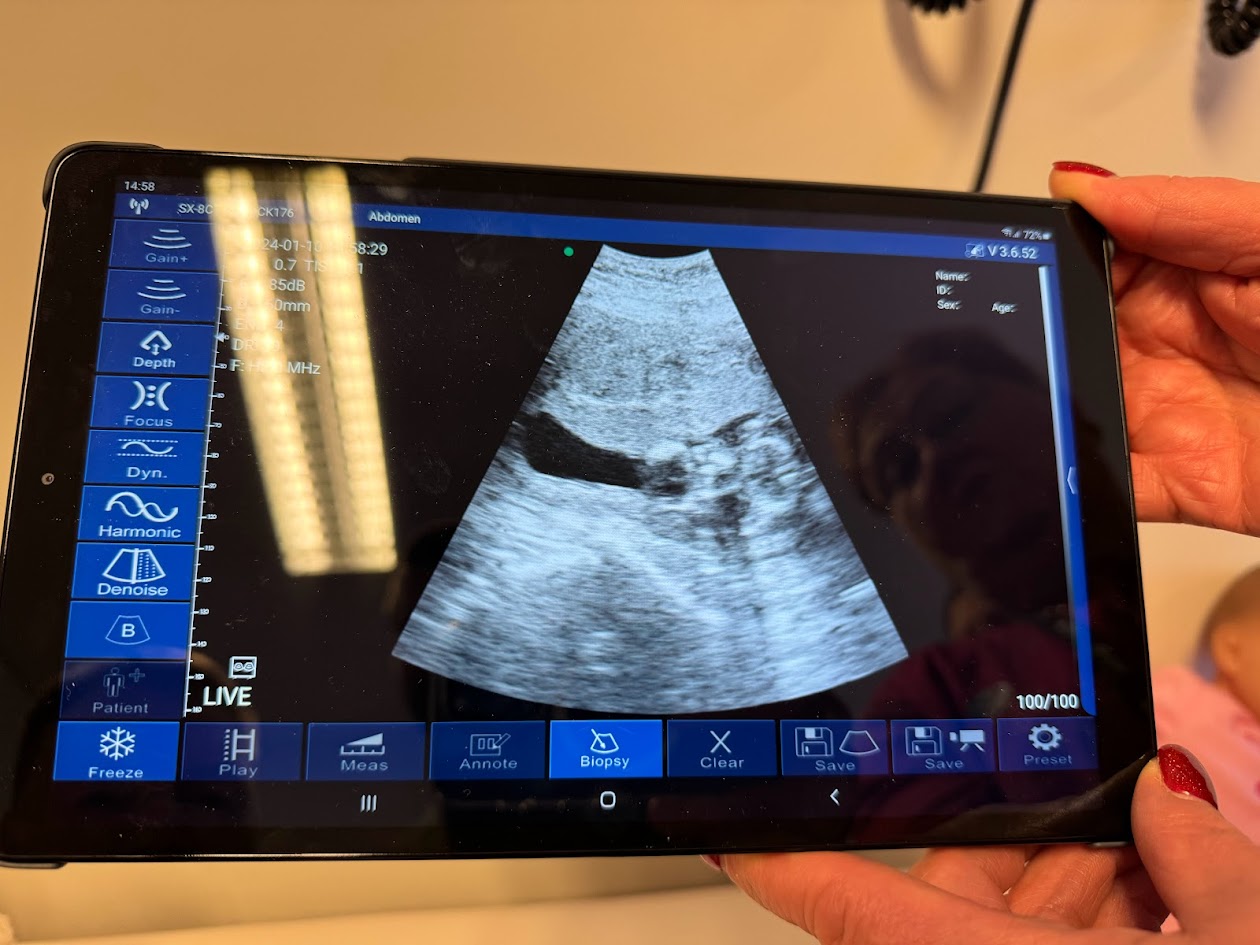

Tækið er af tegundinni Eagle View og virkar sem þrennskonar tæki í einu tæki,

tækið sendir frá sér hljóðbylgjur sem nema viðnámið og sendir lifandi myndbandsupptöku eða myndir beint í spjaldtölvu,

farsíma eða hvað sem er annað sem tekur á móti þráðlausum boðum frá tækinu.

Tækið er bylting fyrir heilsugæslustöðina á Dalvík, þar sem það mun nýtast að mestu í meðgönguverndinni meðal annars til að meta legu fósturs sé það ekki ljóst með klínísku mati.

Einnig er hægt að greina hjartslátt fósturs fyrr á meðgöngu heldur en með því tæki sem fyrir er á heilsugæslunni. Greiningarsónar t.d. 12 vikna og 20 vikna sónarskoðanir munu áfram fara fram á Akureyri. Einnig mun tækið nýtast til að finna vökvasöfnun merki um innvortis blæðingar, gallsteina og flr.